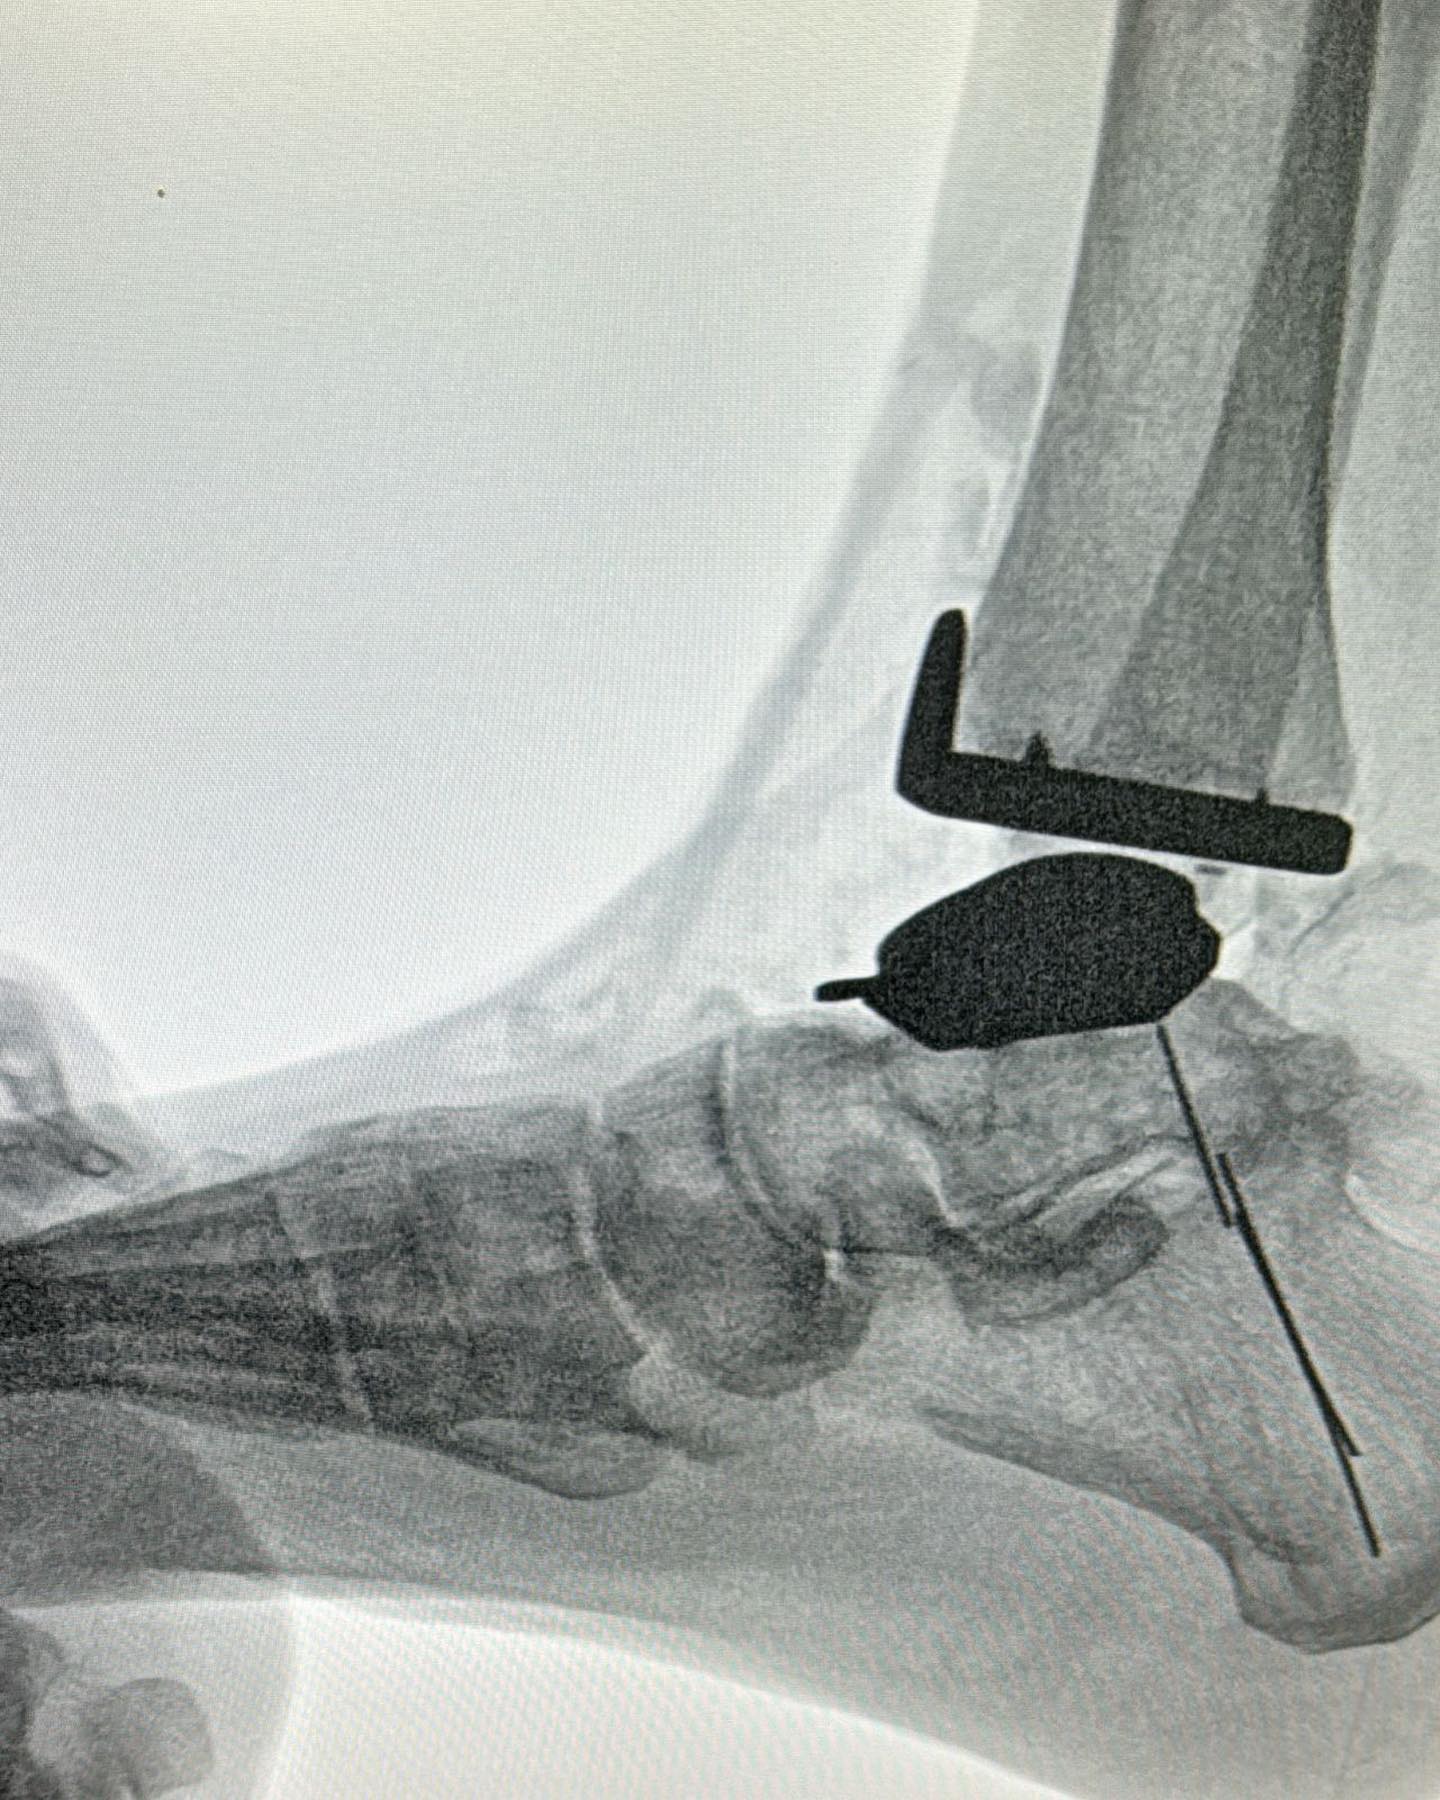

Este procedimiento quirúrgico consiste en sustituir la articulación dañada por una prótesis compuesta de metal y plástico, diseñada para restaurar la movilidad y aliviar el dolor.